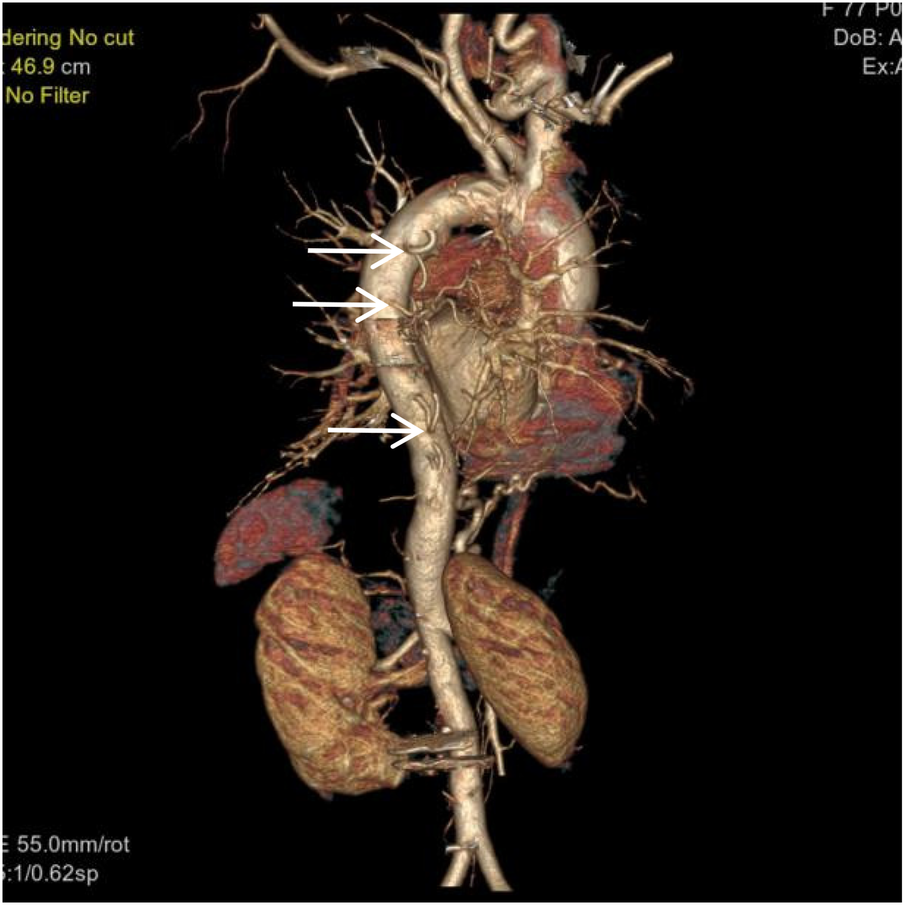

Figure 1

VR image shows absence of the distal main right pulmonary artery, with a rounded and blunt stump (white arrow).

Figure 5

VR image shows multiple large intercostal arteries originating from the right side of the thoracic aorta, with large branches diverging distally into the right lung (white arrow).

Figure 6

VR image shows absence of the distal right pulmonary artery, with a rounded and blunt stump (White arrow). No normal pulmonary artery is visible within the right lung.

Figure 7

Coronal MIP image shows a large branch originating from the right renal artery entering the right lung (white arrow), and a branch of the right subclavian artery entering the right lung (empty arrow). Pulmonary arteries are not visible within the right lung.

Thoracoabdominal aortic CTA and chest CT findings are illustrated in Figures 1–14. There was no evidence of aortic dissection. The right pulmonary artery was absent distal to approximately 3 cm from the bifurcation, with a smooth and rounded defect margin. The main pulmonary artery and its major branches showed no abnormal densities. No right pulmonary artery branches were observed in the right lung. Multiple tortuous arterial branches from the right subclavian artery, descending aorta, and right renal artery supplied the right lung. The right hemithorax was smaller, with localized pleural thickening and adhesions bilaterally. Multiple bronchiectasis with thickened walls and patchy, nodular, and linear opacities encircled the right lung. Increased translucency and several hyperlucent regions were visible in the left lung. CT imaging findings demonstrated: 1. Congenital absence of the right pulmonary artery (RPA), with the right lung supplied by collateral circulation originating from the right subclavian artery, right intercostal arteries, and the right renal artery. 2. Right pulmonary hypoplasia, bronchiectasis of the right lung, accompanied by infection and partial consolidation in the right upper lobe, compensatory hyperinflation of the left lung, and multiple bullae in the left lung. 3. Bilateral localized pleural thickening and adhesions. 4. Osteoporosis and mild flattening of the T6 vertebra and compression fractures of T11 and T12.

Unilateral absence of the pulmonary artery (UAPA), or unilateral pulmonary artery agenesis, is a rare congenital condition caused by developmental malformation of the pulmonary vasculature. The condition often occurs together with congenital heart diseases, including atrial septal defect and tetralogy of Fallot. However, when it occurs without any other congenital heart defects, it is referred to as IUAPA, which is even rarer. Based on the data presented by Bouros et al. (2), the incidence of the condition is approximately 1 in 200,000, often presenting with right-sided predominance. However, relevant data from Chinese statistics is limited. Digital subtraction angiography (DSA) pulmonary angiography remains the gold standard for diagnosing IUAPA. A review of the existing relevant literature indicates that a significant proportion of reported cases have come from the discipline of ultrasound medicine in China (3, 4). However, CTA has gradually gained significance as a clinical examination technique in recent years. This is mainly due to the greater accessibility of CT equipment in comparison to DSA and its numerous advantages, which include rapid and easy application, minimal invasiveness, and its ability to simultaneously assess extravascular pathology (5). Using DSA or CT pulmonary angiography, the imaging typically reveals that the proximal segment of the affected pulmonary artery terminates in a smooth, rounded blind end, with non-opacified pulmonary trunk and distal branches. Due to the single functioning pulmonary artery, the main and contralateral pulmonary artery may appear dilated and tortuous. Extensive systematic collateral arteries develop from the systemic circulation, branching from vessels such as the aorta, intercostal artery, bronchial artery, subclavian artery, internal thoracic artery, internal mammary artery, phrenic artery, renal artery or coronary artery to supply the affected area. Aortic angiography is often used to visualize these systemic-to-pulmonary connections. In the presented case, the thoracic and abdominal aortic CTA clearly demonstrated the absence of the distal right pulmonary artery and the presence of a prominent collateral supply to the right lung from branches of bronchial artery, the right renal artery, right intercostal arteries, and right subclavian artery. Chest CT typically reveals a loss of volume in the affected lung, a shift in the trachea and mediastinum towards the affected side, asymmetric bronchovascular markings, and frequently, dilation of the contralateral pulmonary artery. It is also commonly accompanied by findings such as ipsilateral pneumonia, partial atelectasis, bronchiectasis, heterogeneous emphysema, and pulmonary bullae. The chest CT findings in this case are consistent with this description. During embryogenesis, the pathoanatomical features of UAPA include the development of the main pulmonary artery and the proximal segments of the right and left pulmonary arteries from the ventral portion of the sixth aortic arch. Conversely, the intrapulmonary arteries and their branches originate from the postbranchial pulmonary vascular plexus. If the central pulmonary artery is not fully developed or there is localized obliteration, leading to an inability to form the usual connections and communications with the intrapulmonary arteries, a congenital vascular malformation characterized by the absence of one or both pulmonary arteries is indicated. In the absence of one pulmonary artery, the affected lung is deprived of the blood flow necessary for its pulmonary circulation, which is a part of the dual pulmonary blood supply. Consequently, the affected lung is sustained by bronchial arteries or other systemic collateral vessels for perfusion, resulting in a poorer blood supply compared to the contralateral lung. This has severe consequences for pulmonary development, resulting in pulmonary hypoplasia and volume loss in the affected lung. In addition, hypocapnia develops in the alveoli and respiratory bronchioles as the affected lung's main blood supply comes from systemic arteries that have a low carbon dioxide content. Research has shown that this condition can lead to the triggering of bronchospasm, the reduction of pulmonary ventilation, the impairment of mucociliary clearance in the bronchial walls, and the subsequent occurrence of recurrent respiratory infections. It has been established that hypoventilation and hypoxia in the affected lung can induce pulmonary vascular wall thickening, vasoconstriction, and ultimately lead to pulmonary hypertension(PH) and even right heart failure. PH resulting from UAPA is classified as a form of “segmental pulmonary hypertension”, with a reported incidence ranging from 19% to 44%. Segmental pulmonary hypertension currently refers to a condition where diverse sources of pulmonary blood supply lead to distal pulmonary vascular disease, variably affecting different lung segments (6, 7). The collateral vessels supplying the affected lung are often dysplastic and prone to causing symptoms such as hemoptysis. The cumulative impact of these pulmonary pathologies leads to a variety of clinical and imaging presentations that resemble bronchiectasis, pulmonary tuberculosis, COPD, and pulmonary embolism, none of which are specific. This results in the prolonged misdiagnosis of the majority of patients with these prevalent diseases (8–10). The patient had received treatment for 30 years for diagnoses of pulmonary tuberculosis and COPD, with suboptimal therapeutic outcomes. During this period, multiple chest CT scans were performed; however, a comprehensive assessment of the pulmonary vascular system was not conducted, nor was the potential relationship between the long-standing recurrent pulmonary pathologies and pulmonary vascular developmental abnormalities considered. Instead, the absence of RPA was incidentally identified during CTA performed to investigate the cause of chest pain, with multiple systemic collateral vessels observed supplying the right lung. Concurrent echocardiography revealed no definite intracardiac structural abnormalities. Following a thorough review of the available evidence, the initial diagnoses were found to be consistent with the condition known as IUAPA. Hemoptysis is one of the primary clinical symptoms associated with this particular disease. Combined with chest pain and shortness of breath caused by pulmonary pathology, the clinical picture can resemble pulmonary embolism. Therefore, this disease should be differentiated from pulmonary embolism clinically. Acute pulmonary embolism often shows a significant elevation in plasma D-dimer levels. Although this patient had chest pain, it was ultimately confirmed to be caused by an osteoporotic vertebral compression fracture, involving an element of chance.Current management of this condition primarily focuses on symptomatic treatment, mainly aimed at preventing hemoptysis, infection, and PH. Early intervention in infants and young children through pulmonary revascularization of the affected lung may facilitate normal pulmonary development and reduce adverse outcomes such as PH.